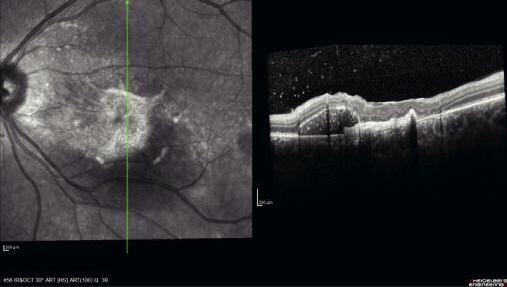

271 Fibrosi maculare post-esplosione: case report di un militare sopravvissuto

M a c u l a r f i b r o s i s a f t e r b o m b e x p l o s i o n : a c a s e r e p o r t a b o u t a survived military man

I traumi da scoppio del bulbo oculare comportano generalmente conseguenze irreversibili per la vista I meccanismi fisiopatogenetici dei danni da onda d’urto sono descritti nel caso riportato dagli autori che forniscono anche i lineamenti di terapia e riabilitazione